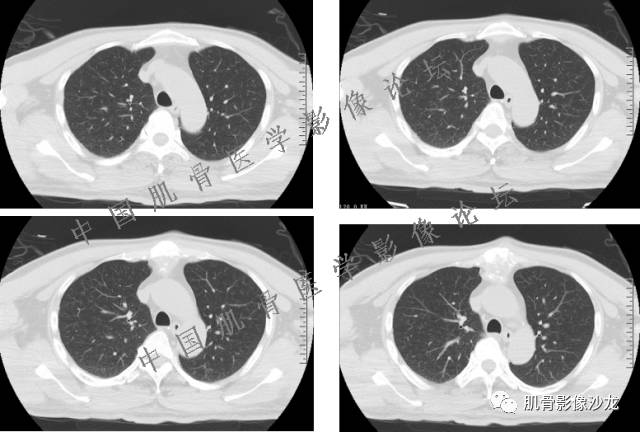

患者2月前无明显诱因下感右腿疼痛、麻木,疼痛呈持续性,发作时无法行走,休息后可缓解。当时无明显肿块,患者遂至当地医院就诊,查X片见右髂骨骨质破坏。6周前患者自觉右髋部渐大肿块,初肿块较小,后肿块逐渐增大,现肿块约12*10cm大小,有压痛。患者遂至我院就诊,查MRI:右髂骨异常信号,伴软组织肿块。ECT、肺CT未见转移。现患者为求进一步治疗,门诊拟“右髂骨肿块 ”收治入院。 患者发病来,神清,精神可,胃纳夜眠可,二便无殊,体重无明显变化。

信号 飞鹰行动:的确应该考虑软骨类肿瘤

飞鹰行动 : 软骨肉瘤内也有纤维组织的

飞鹰行动 : 第一列可以看见T2小结节样高信号,周围有纤维组织环绕

高回青 : 另外还可以见到扇贝状分叶

1、软骨肉瘤可以有膨胀性骨质破坏(病例3,4),可以有溶骨性骨质破坏(病例2),局部皮质因为破坏变薄,中断 ;

2、软骨基质T2WI高信号,软骨小叶分叶状,也就会出现高老师提到的骨内膜扇贝形压迹。一般认为骨内膜扇贝形压迹超过骨皮质厚度的2/3是软骨肉瘤在长管状骨的特征性表现。如上图。3、软组织肿块或肿胀;

4、 钙化,环形,弓形,边缘模糊 ;

5、增强后进行性延迟,不均匀分割状强化, 会强化的纤维间隔,软骨小叶不会强化,关于老师们说到的钙化,软骨肉瘤不一定会有钙化 。